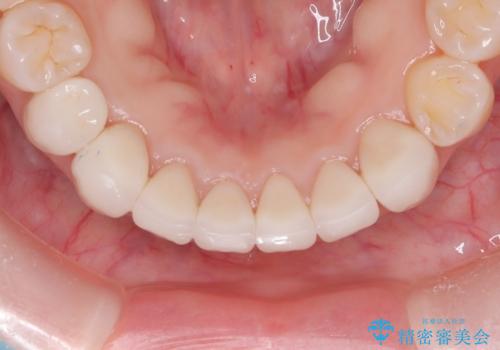

【オールセラミック】下の前歯が痛い。

- 以前に治療した前歯が痛むことを主訴に来院されました。

根っこに病気があり、根管治療から被せ物まで治療を行いました。

根管治療を行った後、3ヶ月間治癒の確認をしてからオールセラミックスペシャルで治療を行いました。